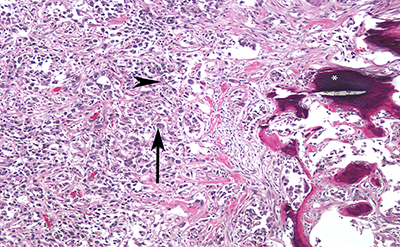

We present a 62-year-old man with a history of hypertension and obesity who developed gross hematuria after a fall from his bicycle. When the hematuria persisted, magnetic resonance imaging (MRI) and computed tomography (CT) were performed, revealing a 3.6 x 3.2 x 2.5 cm left upper pole renal mass (Figure 1 A). The mass was mostly endophytic, though still present at the cortico-medullary junction, so RCC and urothelial carcinoma (UC) were both potential diagnoses.

The kidney was fully mobilized and the main renal artery was clamped, then extirpation was attempted. However, upon entering the collecting system, the tumor was found to be inside the lumen (Figure 1 B). The immediate concern was for UC, and the procedure was converted to a nephroureterectomy.  The patient recovered from surgery and was discharged from the hospital on post-operative day two.

Figure 1. A, Magnetic resonance imaging (MRI) showing endophytic, posterior upper pole left renal mass (indicated by *), suspicious for carcinoma.  B, Intraoperative photograph showing grossly invasive mass involving the lumen of the collecting system.  T – Tumor; CS – collecting system; TF – tumor fossa.